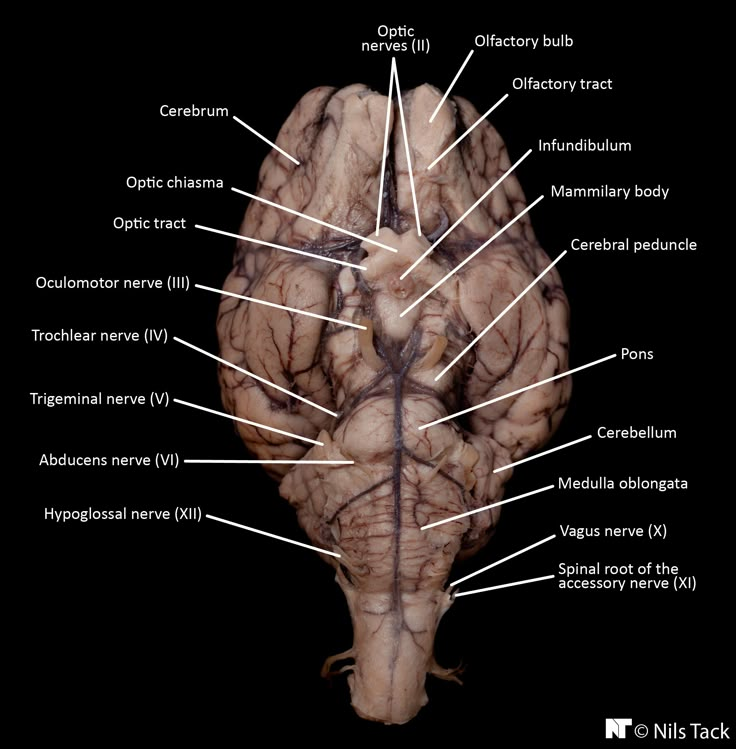

pons

“bridge that links medulla oblongata to thalamus

medulla oblongata

houses autonomic centers

pituitary gland

“master” gland of endocrine system - on the middle of bottom side of brain

infundibulum

optic chiasm